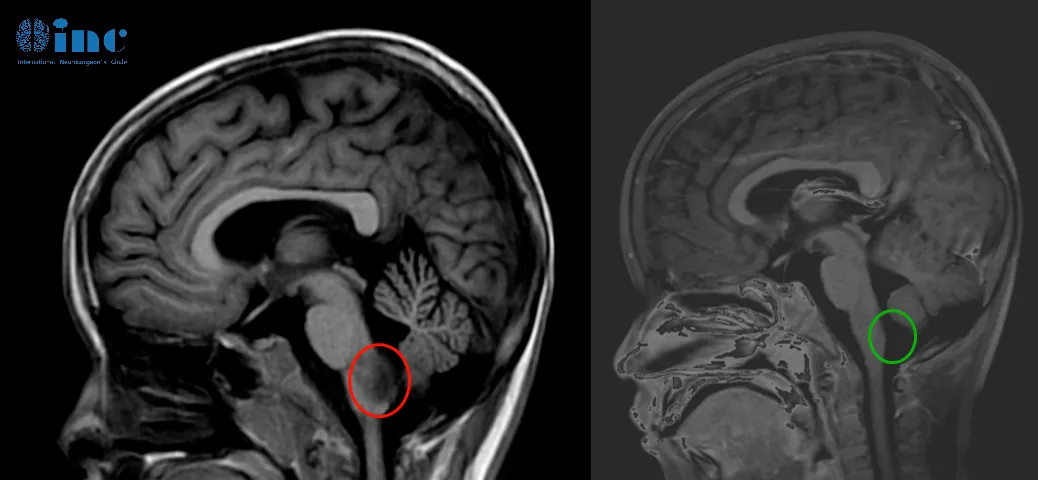

康康术前术后影像对比